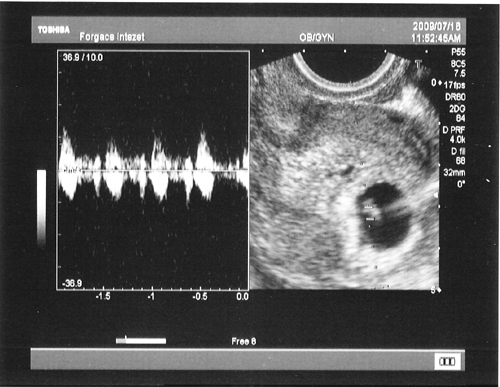

Tehát, ma voltunk UH-n.

Az eredmény:

TVS során a terhes méh üregében egy szabályos 19 mm-es petezsák ábrázolódik. Benne egy szabályos másodlagos szikhólyag és egy embryo látható. CRL: 4,7 mm. Vetületében ritmusos szívcsőpulzáció igazolható. Mindkét oldalon stimulált petefészkek, a Douglasban szabad hasűri folyadék nem látható.

Hallottuk a szívhangját, annyira csodás érzés, párom teljesen oda meg vissza volt a gyönyörtől...

Íme a képek:

Babócánk és az ő szívhangja...

Babócánk és az ő szívhangja...